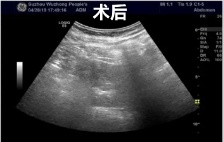

2、超声引导下囊肿抽液硬化治疗,肝囊肿、肾囊肿穿刺抽液硬化治疗,盆腔囊肿穿刺抽液硬化治疗,甲状腺、乳腺囊肿穿刺抽液治疗。

肝囊肿经皮超声引导性介入治疗